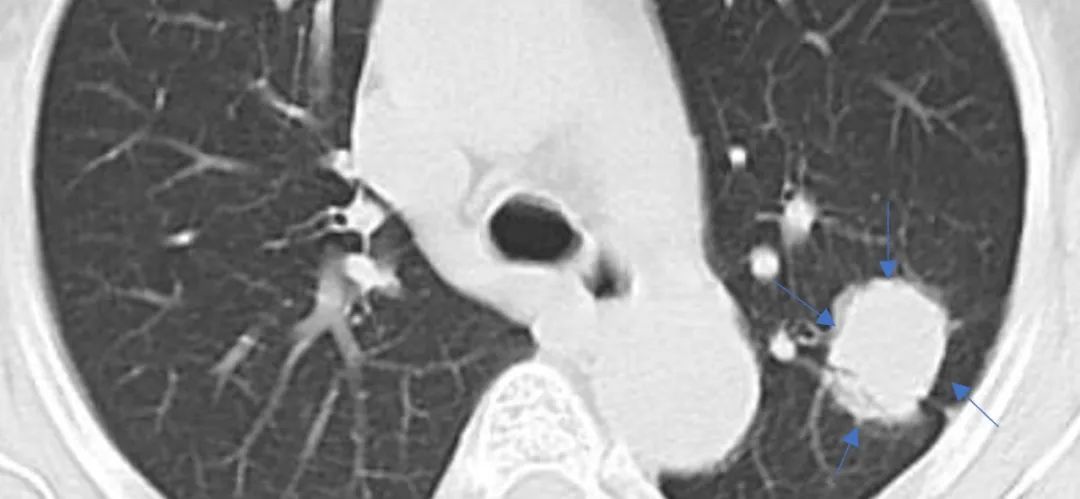

通过以下三张图片

可以有一个很好的理解

纯磨玻璃结节,可见内部血管影

混合磨玻璃结节,周围蓝色箭头所示为磨玻璃成分,中央红色箭头为实性成分